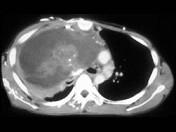

问题 男,37岁,咳嗽,咯血2月余,偶尔咳出钙化物,请结合影像学检查,选出最可能的诊断 ( )

选项 A.畸胎瘤 B.肺癌 C.胸腺瘤 D.淋巴管瘤 E.淋巴瘤

答案 A